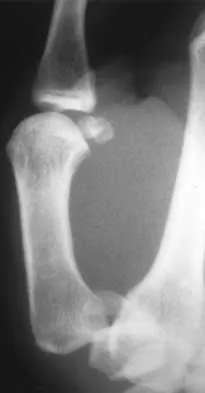

A 15-year-old boy falls from his bicycle and sustains an injury to his elbow. Prereduction radiographs are shown in Figure 12a. Closed reduction is performed without difficulty and postreduction radiographs are shown in Figure 12b. What is the next most appropriate step in treatment?

Elbow dislocations in children are rare injuries and usually result from a fall on an outstretched arm. The incidence of these injuries increases as patients age and concurrently the incidence of supracondylar humerus fractures decreases. In adolescent patients, simple elbow dislocations are treated with splint immobilization and the initiation of physical therapy once comfortable. The practitioner must be aware of structures that may get caught in the joint on reduction. These include the median nerve as well as the medial epicondyle. In this patient, the radiographs reveal a medial epicondyle fracture. Postreduction radiographs show the joint to be incongruous secondary to intra-articular displacement. At this point, the most appropriate treatment is to perform an open reduction and repair of the medial epicondyle fragment. Rasool MN: Dislocations of the elbow in children. J Bone Joint Surg Br 2004;86:1050-1058.